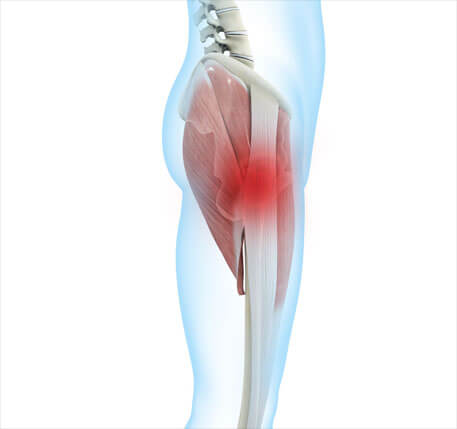

Piriformis syndrome

Piriformis syndrome is a neuromuscular disorder that occurs when the piriformis muscle compresses the sciatic nerve. The piriformis muscle is important in lower body movement as it stabilises the hip joint and helps to lift and rotate the thigh. The sciatic nerve runs along or through the piriformis muscle, down the back of the leg and ends in the feet. A spasm of the piriformis muscle can cause compression of the nerve and piriformis syndrome occurs (11).

Hip pain in piriformis syndrome occurs in the buttock and lateral aspect of the hip, but can occasionally be felt along the front of the thigh. Pain increases during activity, when getting out of bed or when sitting for long periods of time. It can be triggered by a specific movement that causes the pain to spread along the course of the sciatic nerve down the leg.

Individuals report tingling, sharp pain spreading up the leg and numbness in the buttocks. The pain can be very severe (11). It is often the case that piriformis syndrome is mistaken for sciatica, where there is pathology of the discs of the lumbar spine and, as a result, the nerve is compressed in the area of the spinal canal exit. They are distinguished by a good clinical examination and diagnostic imaging.